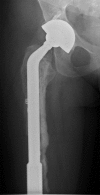

Custom-made endoprostheses can be linked to existing well-fixed implants in the treatment of complex periprosthetic femoral fractures. By adopting this salvage approach, secure implants can be retained in favour of patients undergoing more tissue disruptive procedures such as total femoral replacements. In this piece, we present a unique case illustrating a salvage strategy for treating a failed cement-linked salvage endoprosthesis, a complex scenario which to our knowledge has never before been reported.